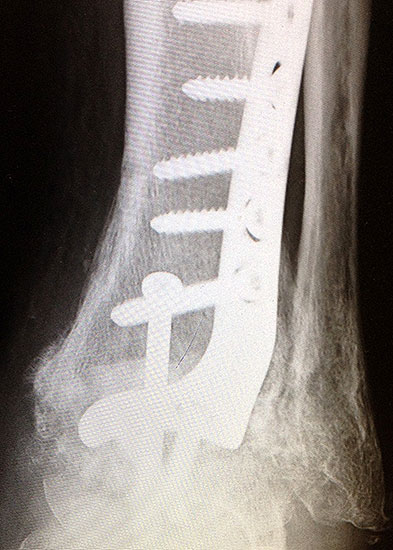

Die Verwendung von präformierten winkelstabilen Titan-Konturplatten gewährleist eine sehr rigide Versorgung und stellen gerade bei malazischem Knochen oder der Erfordernis einer frühen sehr hohen Stabilität ein sicheres allerdings kostenintensives Verfahren dar (Abb. 8 a-k, Abb. 9 a - d). Von der Industrie werden verschiedene Plattensysteme angeboten, teilweise mit polyaxialer Schraubenplatzierung, sowie die bedarfsweise Kombination einer gelenküberschreitenden Zugschraube mit winkelstabilen Schrauben.

Abbildung 8b

Abbildung 8c